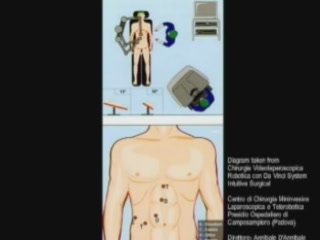

Laparoscopic Antrectomy with..

Laparoscopic Antrectomy with..

R. Matteotti, MD; Greg Dakin, MD; Brian Jacob, MD; Michel Gagner, MD, FACS; William Inabnet, MD, FAC / CINE-MED